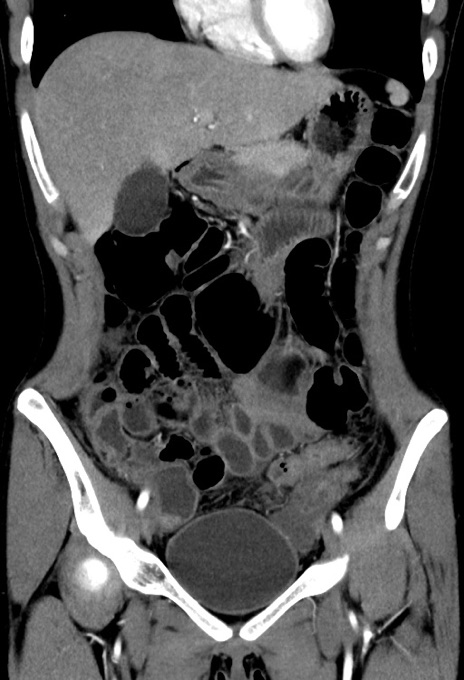

横断像

【症例】20歳代女性

【主訴】嘔吐、下腹部痛

【現病歴】昨日夕食後に嘔吐し下腹部痛が出現。本日になっても嘔吐持続し改善しないため来院。

【身体所見】意識清明、BT 37.2℃、BP 108/67mmHg、腹部:平坦、やや硬、下腹部正中から右にかけて圧痛あり、反跳痛軽度あり、tapping pain(+)。

【データ】WBC 13600、CRP 14.94